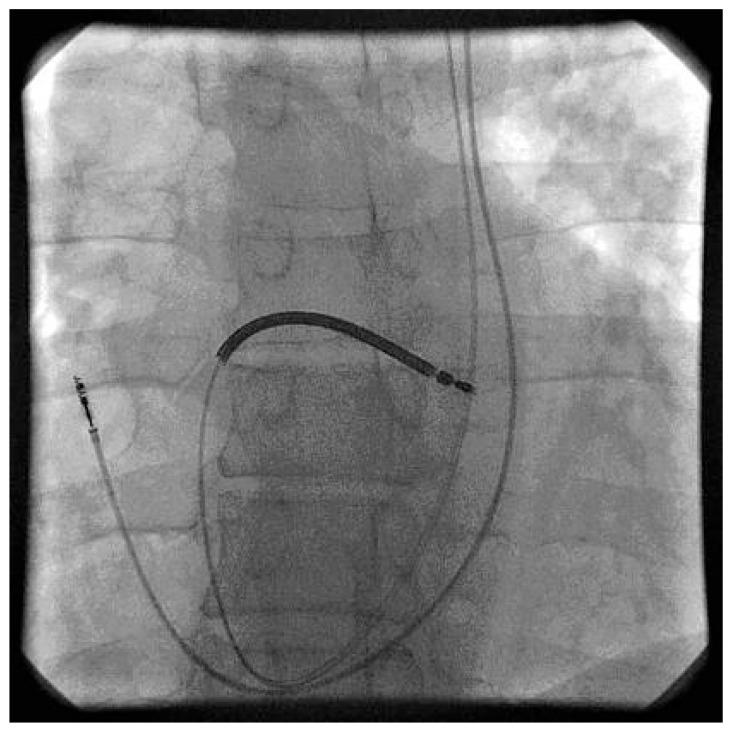

We report a case of persistent left superior vena cava (PLSVC) incidentally recognized during the implantation of a cardioverter-defibrillator. PLSVC is the most common venous anomaly of the thorax and drains into the right atrium. There are a lot of publications reporting success of pacemaker or defibrillator lead implantations via PLSVC. In this article we present the technique of approaching the right ventricle and right atrium via PLSVC; sometimes this method can be as straightforward as the classical way. Therefore, if PLSVC is recognized intra-operatively, we suggest continuing left-sided implantation, and considering a right venous access only in case of failure.

我们报告了一例在植入心脏复律除颤器时偶然发现的持续性左上腔静脉(PLSVC)。PLSVC 是胸部最常见的静脉异常,汇入右心房。有很多出版物报道了通过 PLSVC 成功植入起搏器或除颤器导线。在本文中,我们介绍了经 PLSVC 进入右心室和右心房的方法;有时,这种方法与经典方法一样简单直接。因此,如果在手术中发现 PLSVC,我们建议继续进行左侧植入,如果出现失败情况,再考虑右侧静脉入路。